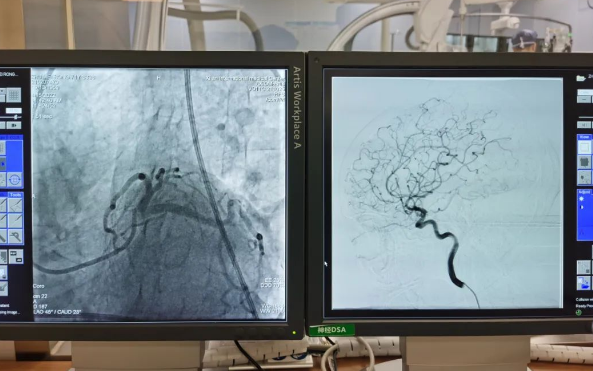

術(shù)前準(zhǔn)備就緒后,心內(nèi)二病區(qū)曾廣偉主任、高釗副主任醫(yī)師、神外科陸丹副主任醫(yī)師共同為患者行腦血管造影術(shù) 冠狀造影術(shù)。術(shù)后,朱奶奶恢復(fù)良好。

陸丹副主任醫(yī)師介紹,由于腦血管疾病和心血管疾病有著共同的病理變化基礎(chǔ)——動脈粥樣硬化,臨床中,兩類疾病交叉存在的情況十分多見。“心腦同治”的模式不僅能讓患者獲得較好治療,還能夠降低患者就醫(yī)的時間成本和經(jīng)濟(jì)成本。